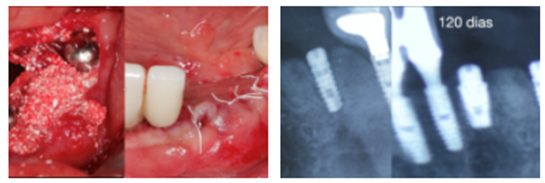

Dessa maneira, foram agregadas as câmaras de cicatrização no corpo do HE Switch e do HI Switch – uma característica do implante Maestro que, comprovadamente, acelera e melhora a qualidade da osseointegração. Além disso, o conceito de redução de plataforma (plataforma switching) entre o pilar e o implante promove menor perda da crista ósseo ao redor dos implantes, mais espaço para a elaboração do perfil de emergência das coroas e facilita a seleção de pilares.

A nova linha é indicada para todas as situações clínicas e, quando inserido até 1 mm infraóssea, apresenta ausência ou redução significante na saucerização ao seu redor, algo que nunca foi possível para implantes HE e HI. Essa macrogeometria possibilita uma osseointegração em menos tempo e com qualidade, sendo possível realizar carga imediata, tardia ou precoce (com dois meses).

“A nova linha é excelente para implante imediato pós-extração. Venho utilizando sistematicamente nos casos de regeneração óssea guiada, principalmente nos aumentos verticais. Um diferencial é o fato desse implante possuir no topo uma parte de metal polido (0,25 mm de altura), sobretudo para casos de aumento vertical, onde não temos um controle de como e o quanto esse novo osso vai remodelar. Aliado a tudo isso, há a plataforma switching que tem como benefício afastar o microgap entre a conexão e o implante dos tecidos peri-implantares, minimizando as perdas causadas pelo infiltrado bacteriano e contribuindo para a estabilidade do osso marginal ao redor do implante.”

“A tecnologia do implante cone-morse Maestro (macrogeometria e plataforma switching) agora está presente nos implantes Hexágono Interno e Externo. Eu utilizo implante cone-morse, mas agora existe a possibilidade de utilizar os implantes de conexões hexagonais com maior segurança na osseointegração. A plataforma switching presente nos implantes HE e HI Switch permite, em algumas situações, que possamos inserir os implantes ligeiramente abaixo da crista óssea, beneficiando assim a formação óssea ao seu redor, protegendo o implante e respeitando o espaço para uma melhor neoformação do osso e do tecido mole.”